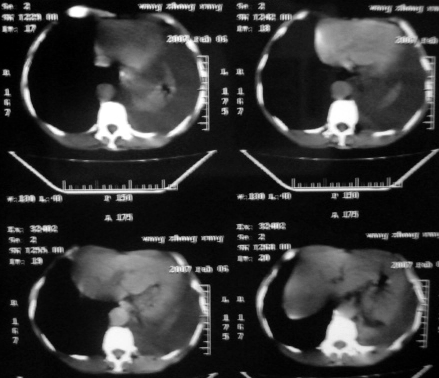

男,54岁,咳嗽,气喘半年,胸痛一月.

血性胸水

左侧胸腔积液 斜裂积液 心包积液 左肺不张 考虑左肺ca并胸膜心包转移。

支持左肺下叶中心型肺癌(累及舌叶)伴阻塞性肺炎、膨胀不全、胸腔积液、心包少量积液。

考虑左肺下叶中央型肺癌伴阻塞性肺炎及肺不张,纵隔受累可能,胸膜转移。

左肺下叶中心型肺癌,伴阻塞性肺炎、左胸腔积液、心包少量积液。